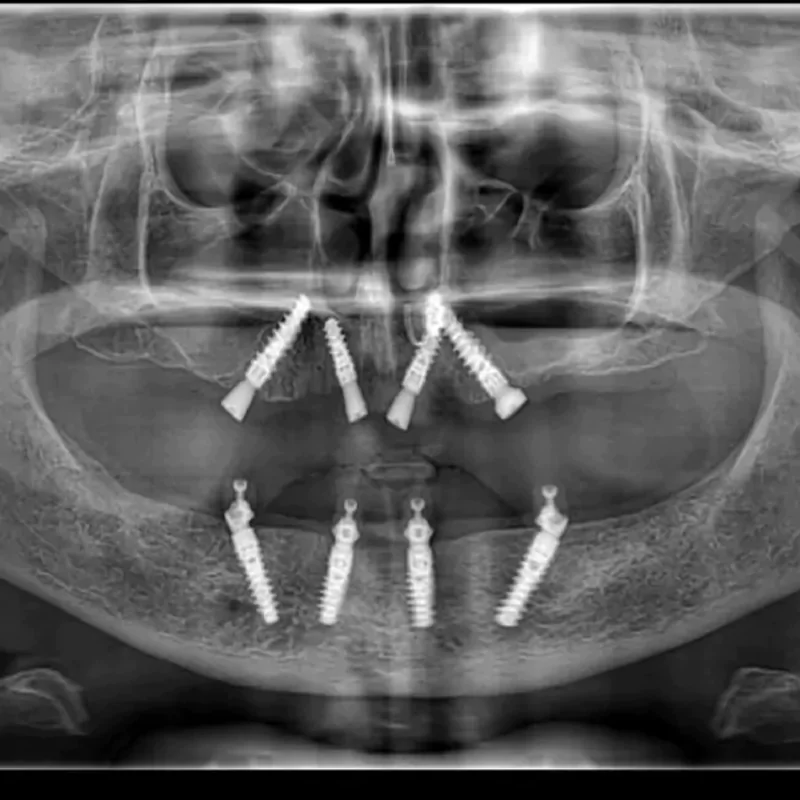

All-on-4 Implants

It is a revolutionary concept in which only four implants support an entire arch of teeth. It is minimally invasive and cost-effective.